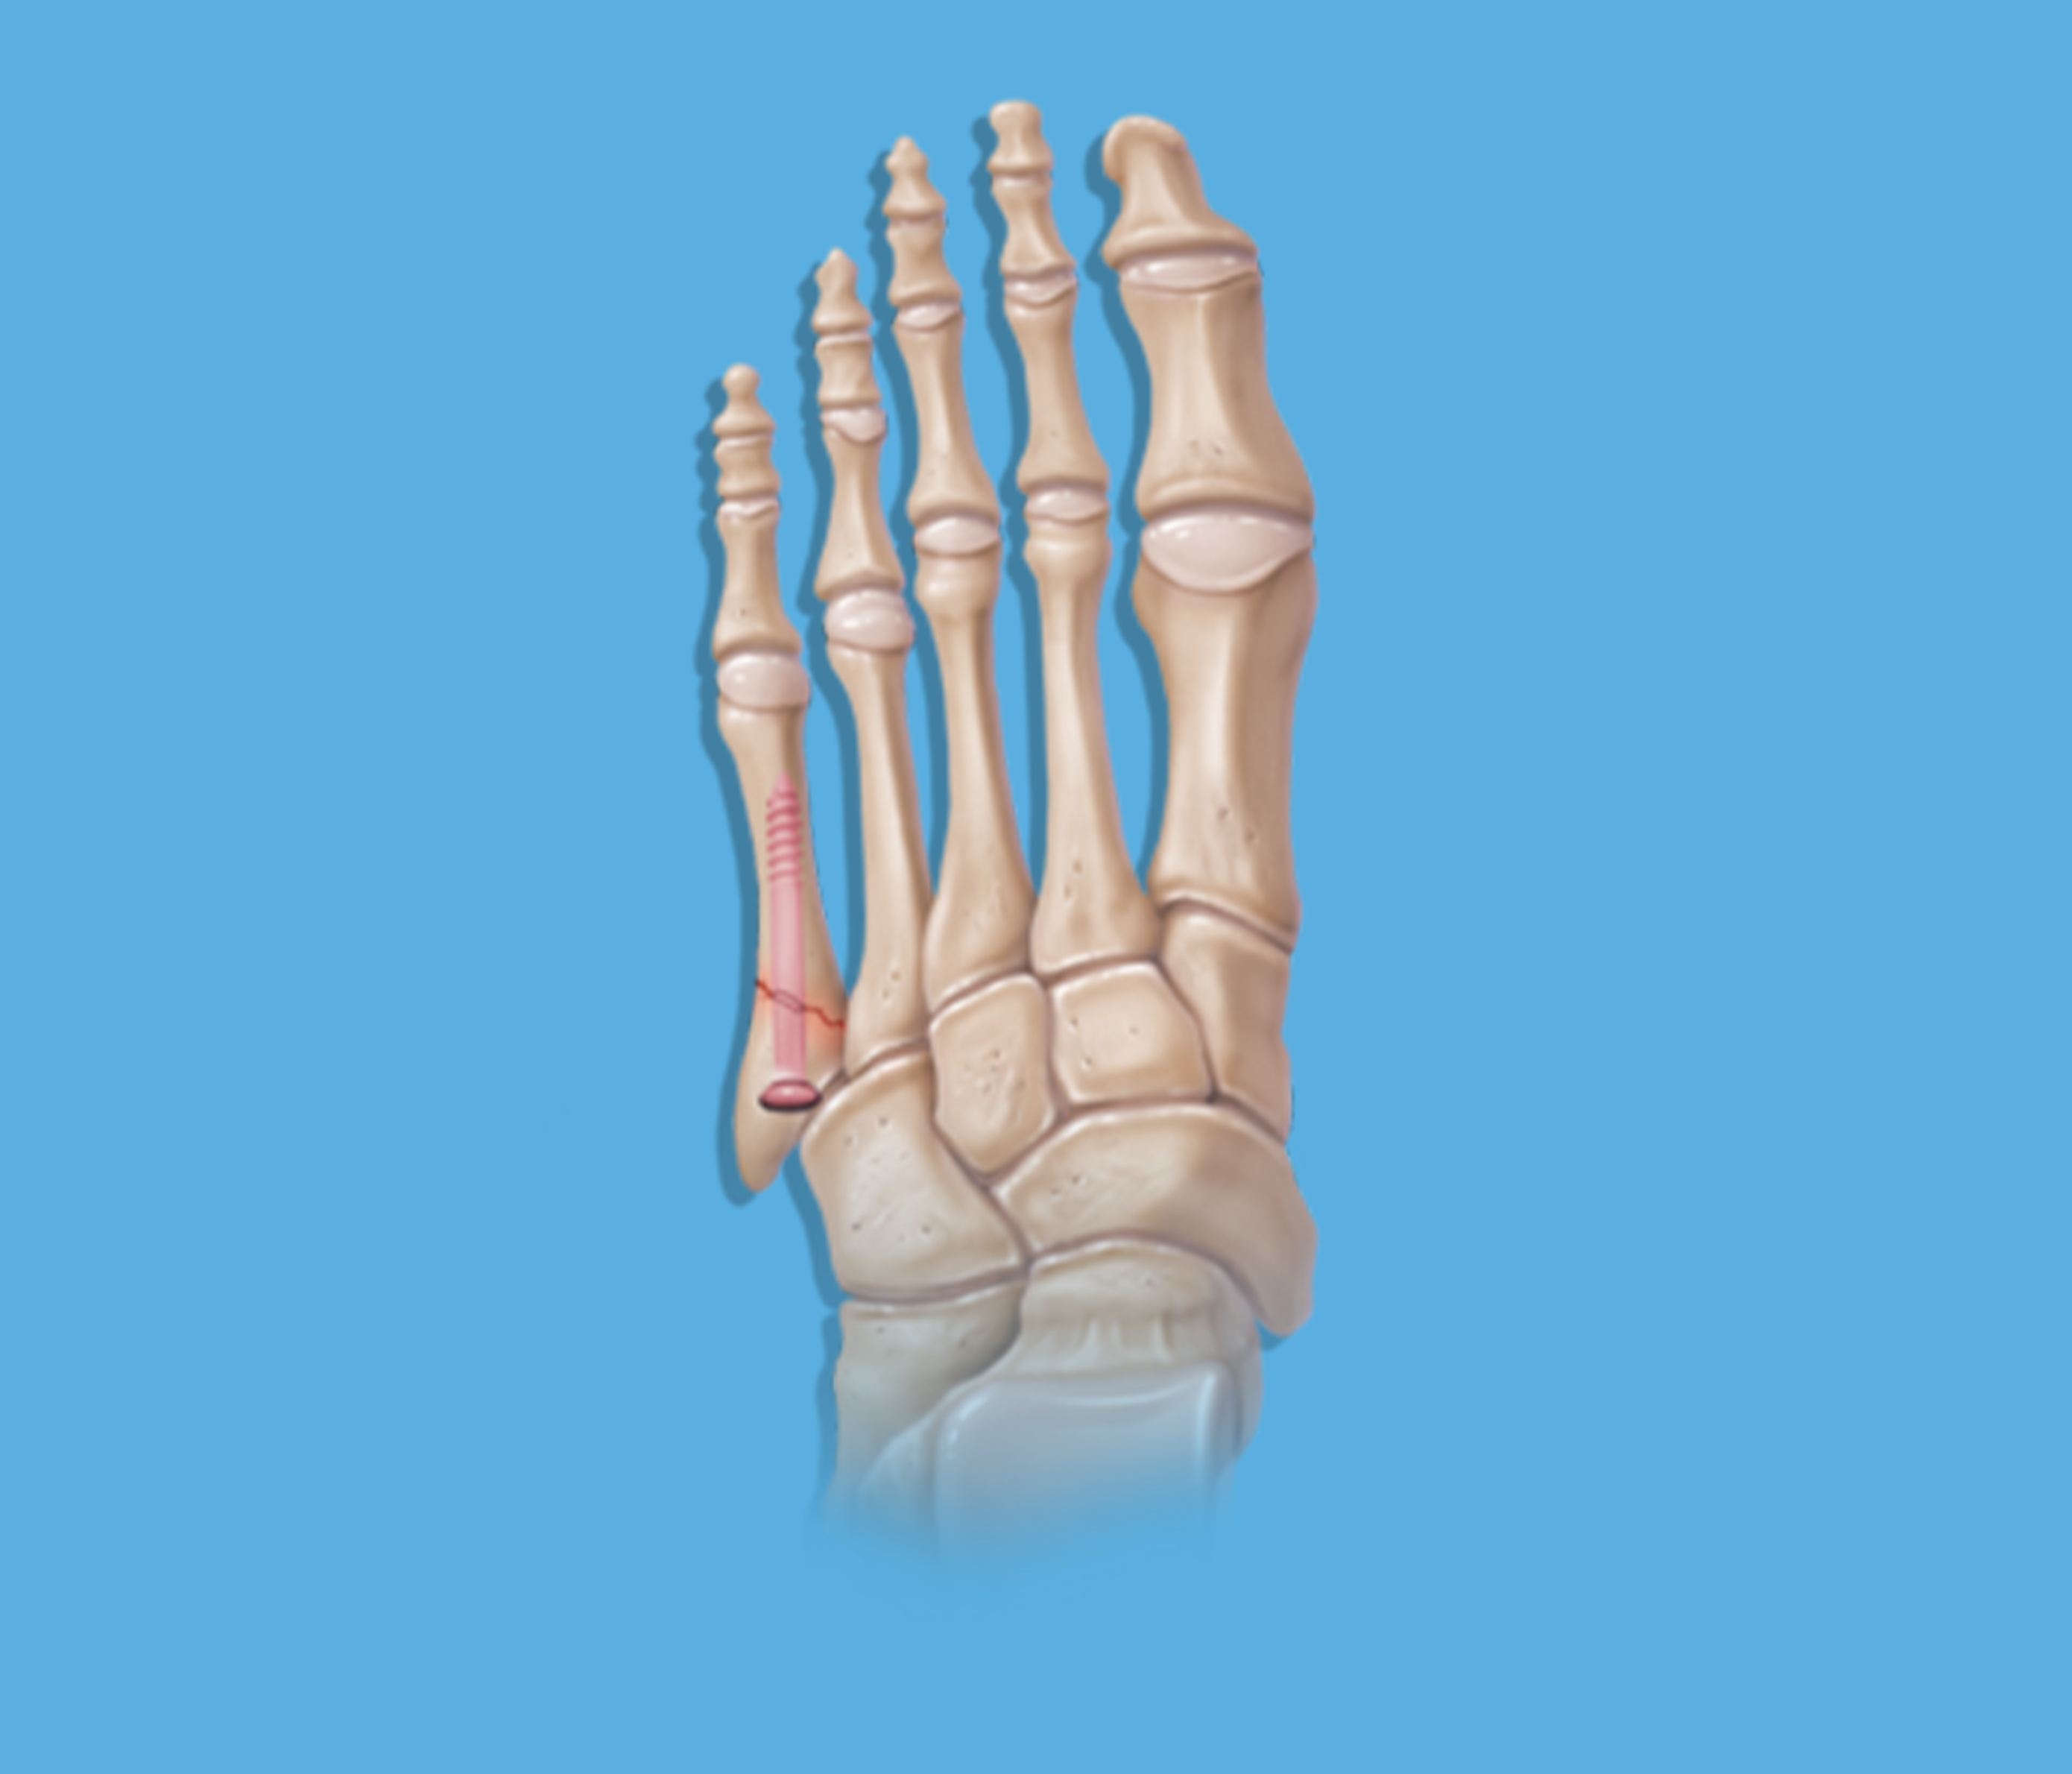

Fracturas Del 5to Metatarso Ilustración del Vector Ilustración de Fractura Hueso Quinto Metatarsiano El quinto hueso metatarsiano es el que mayormente se fractura por alguna causa repentina (lesión ó golpe). Este hueso puede fracturarse en varios puntos a lo largo de su. La fractura del quinto metatarsiano es una fractura muy habitual en la población que en la mayoría de las ocasiones se repara sin dejar ningún problema secundario. Un tipo común de. Fractura Hueso Quinto Metatarsiano.